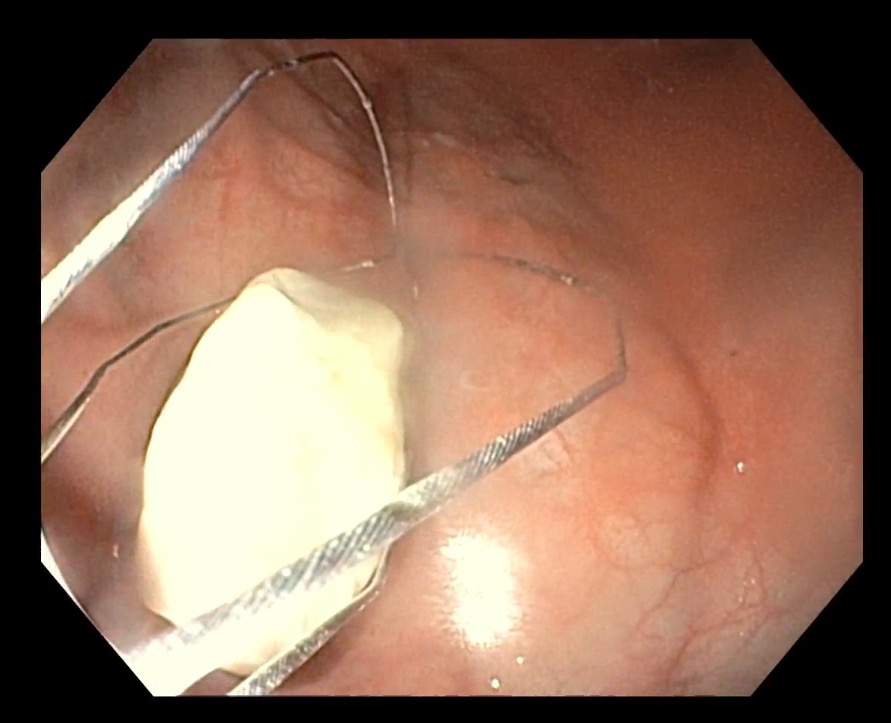

内視鏡の映像。バスケット型の先端を広げたり閉じたり出来るため、石を掴むことができます。